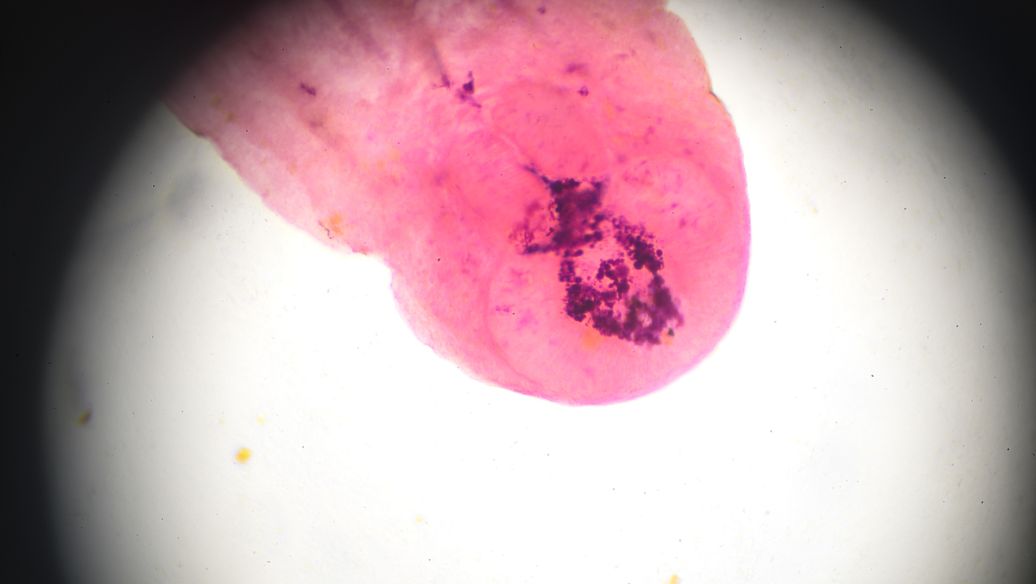

陈某某,女,36岁。外阴瘙痒,白带多,如豆腐状已1年余。白带镜检霉菌(+++)。采用上方,1个疗程后症状减轻;3个疗程后,症状消失,阴道分泌物镜检结果为霉菌阴性c[四川中医,1986;(11):37]